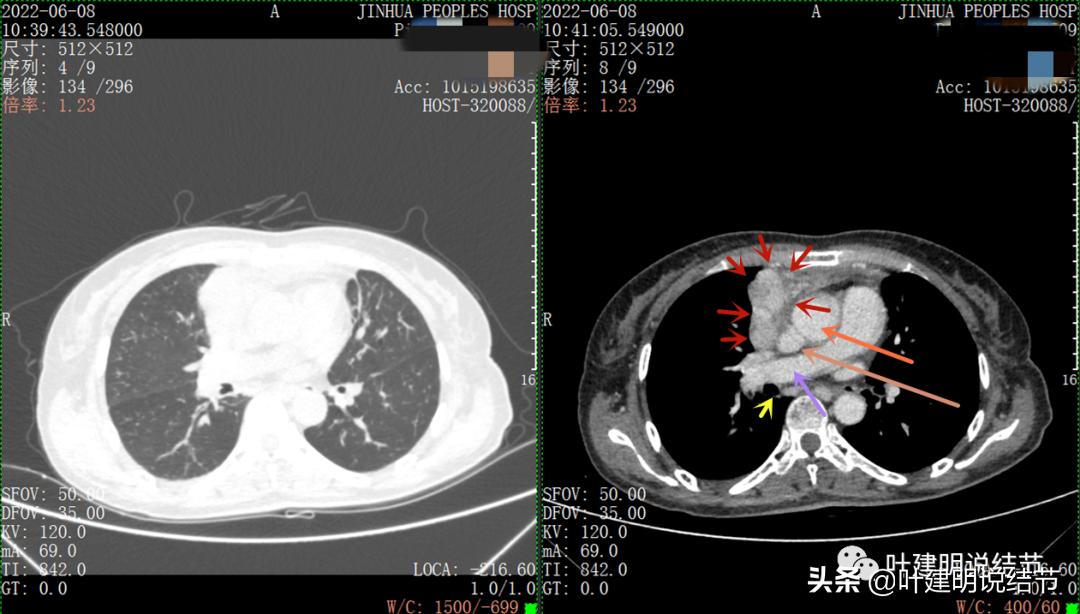

再来看看她的CT增强图像:

以下图片左侧是肺窗,右侧是纵隔窗。红色箭头示病灶,桔色箭头示无名静脉,黄色箭头示支气管,砖色箭头示上腔静脉,蓝色箭头示主动脉,紫色箭头示肺动脉。

病灶占据前纵隔从上到下全程,多中心,密度不均,对心脏与大血管有压迫,没有明显侵犯

特别显示与无名静脉的关系

上图示最大横断位达5厘米